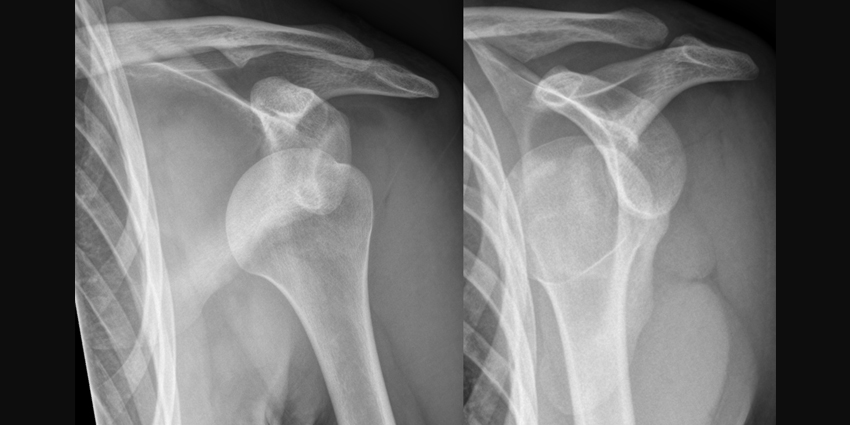

Patients with a primary anterior glenohumeral dislocation experience lower rates of recurrent instability with arthroscopic stabilization than with immobilization in external rotation, according to a new study.

“Arthroscopic stabilization has been established as a superior treatment option for primary glenohumeral instability when compared with immobilization in internal rotation. However, immobilization in external rotation has recently gained interest as a viable nonoperative treatment option for patients with shoulder instability,” wrote researchers.